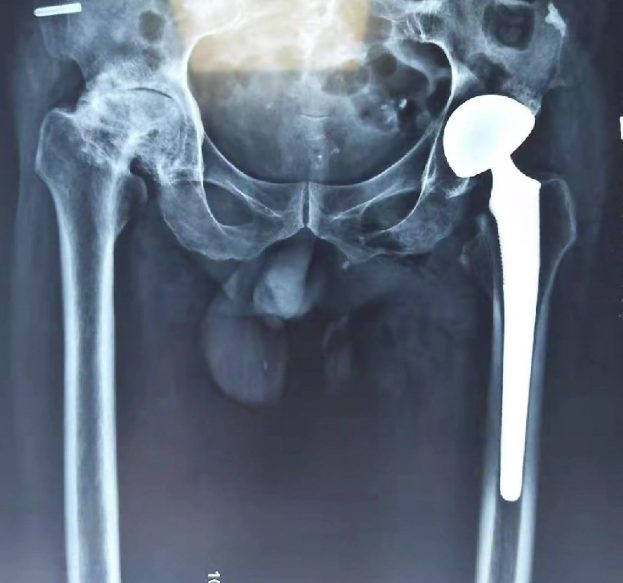

來到棗莊誠德骨科醫(yī)院救治后,得到了專家的精心治療。據(jù)劉德俊院長介紹,薛先生被診斷為雙側(cè)股骨頭壞死,雙側(cè)全髖關(guān)節(jié)骨性關(guān)節(jié)炎,骨質(zhì)增生非常嚴重,整個髖關(guān)節(jié)不能活動,走路呈剪刀腿形狀,治療比較復雜,有一定困難,為此,全院組織專家進行了會診,拿出了一套系統(tǒng)、安全,科學,先進的治療方案。由于他的病情比較復雜,專家組分兩次進行了手術(shù),手術(shù)很成功。